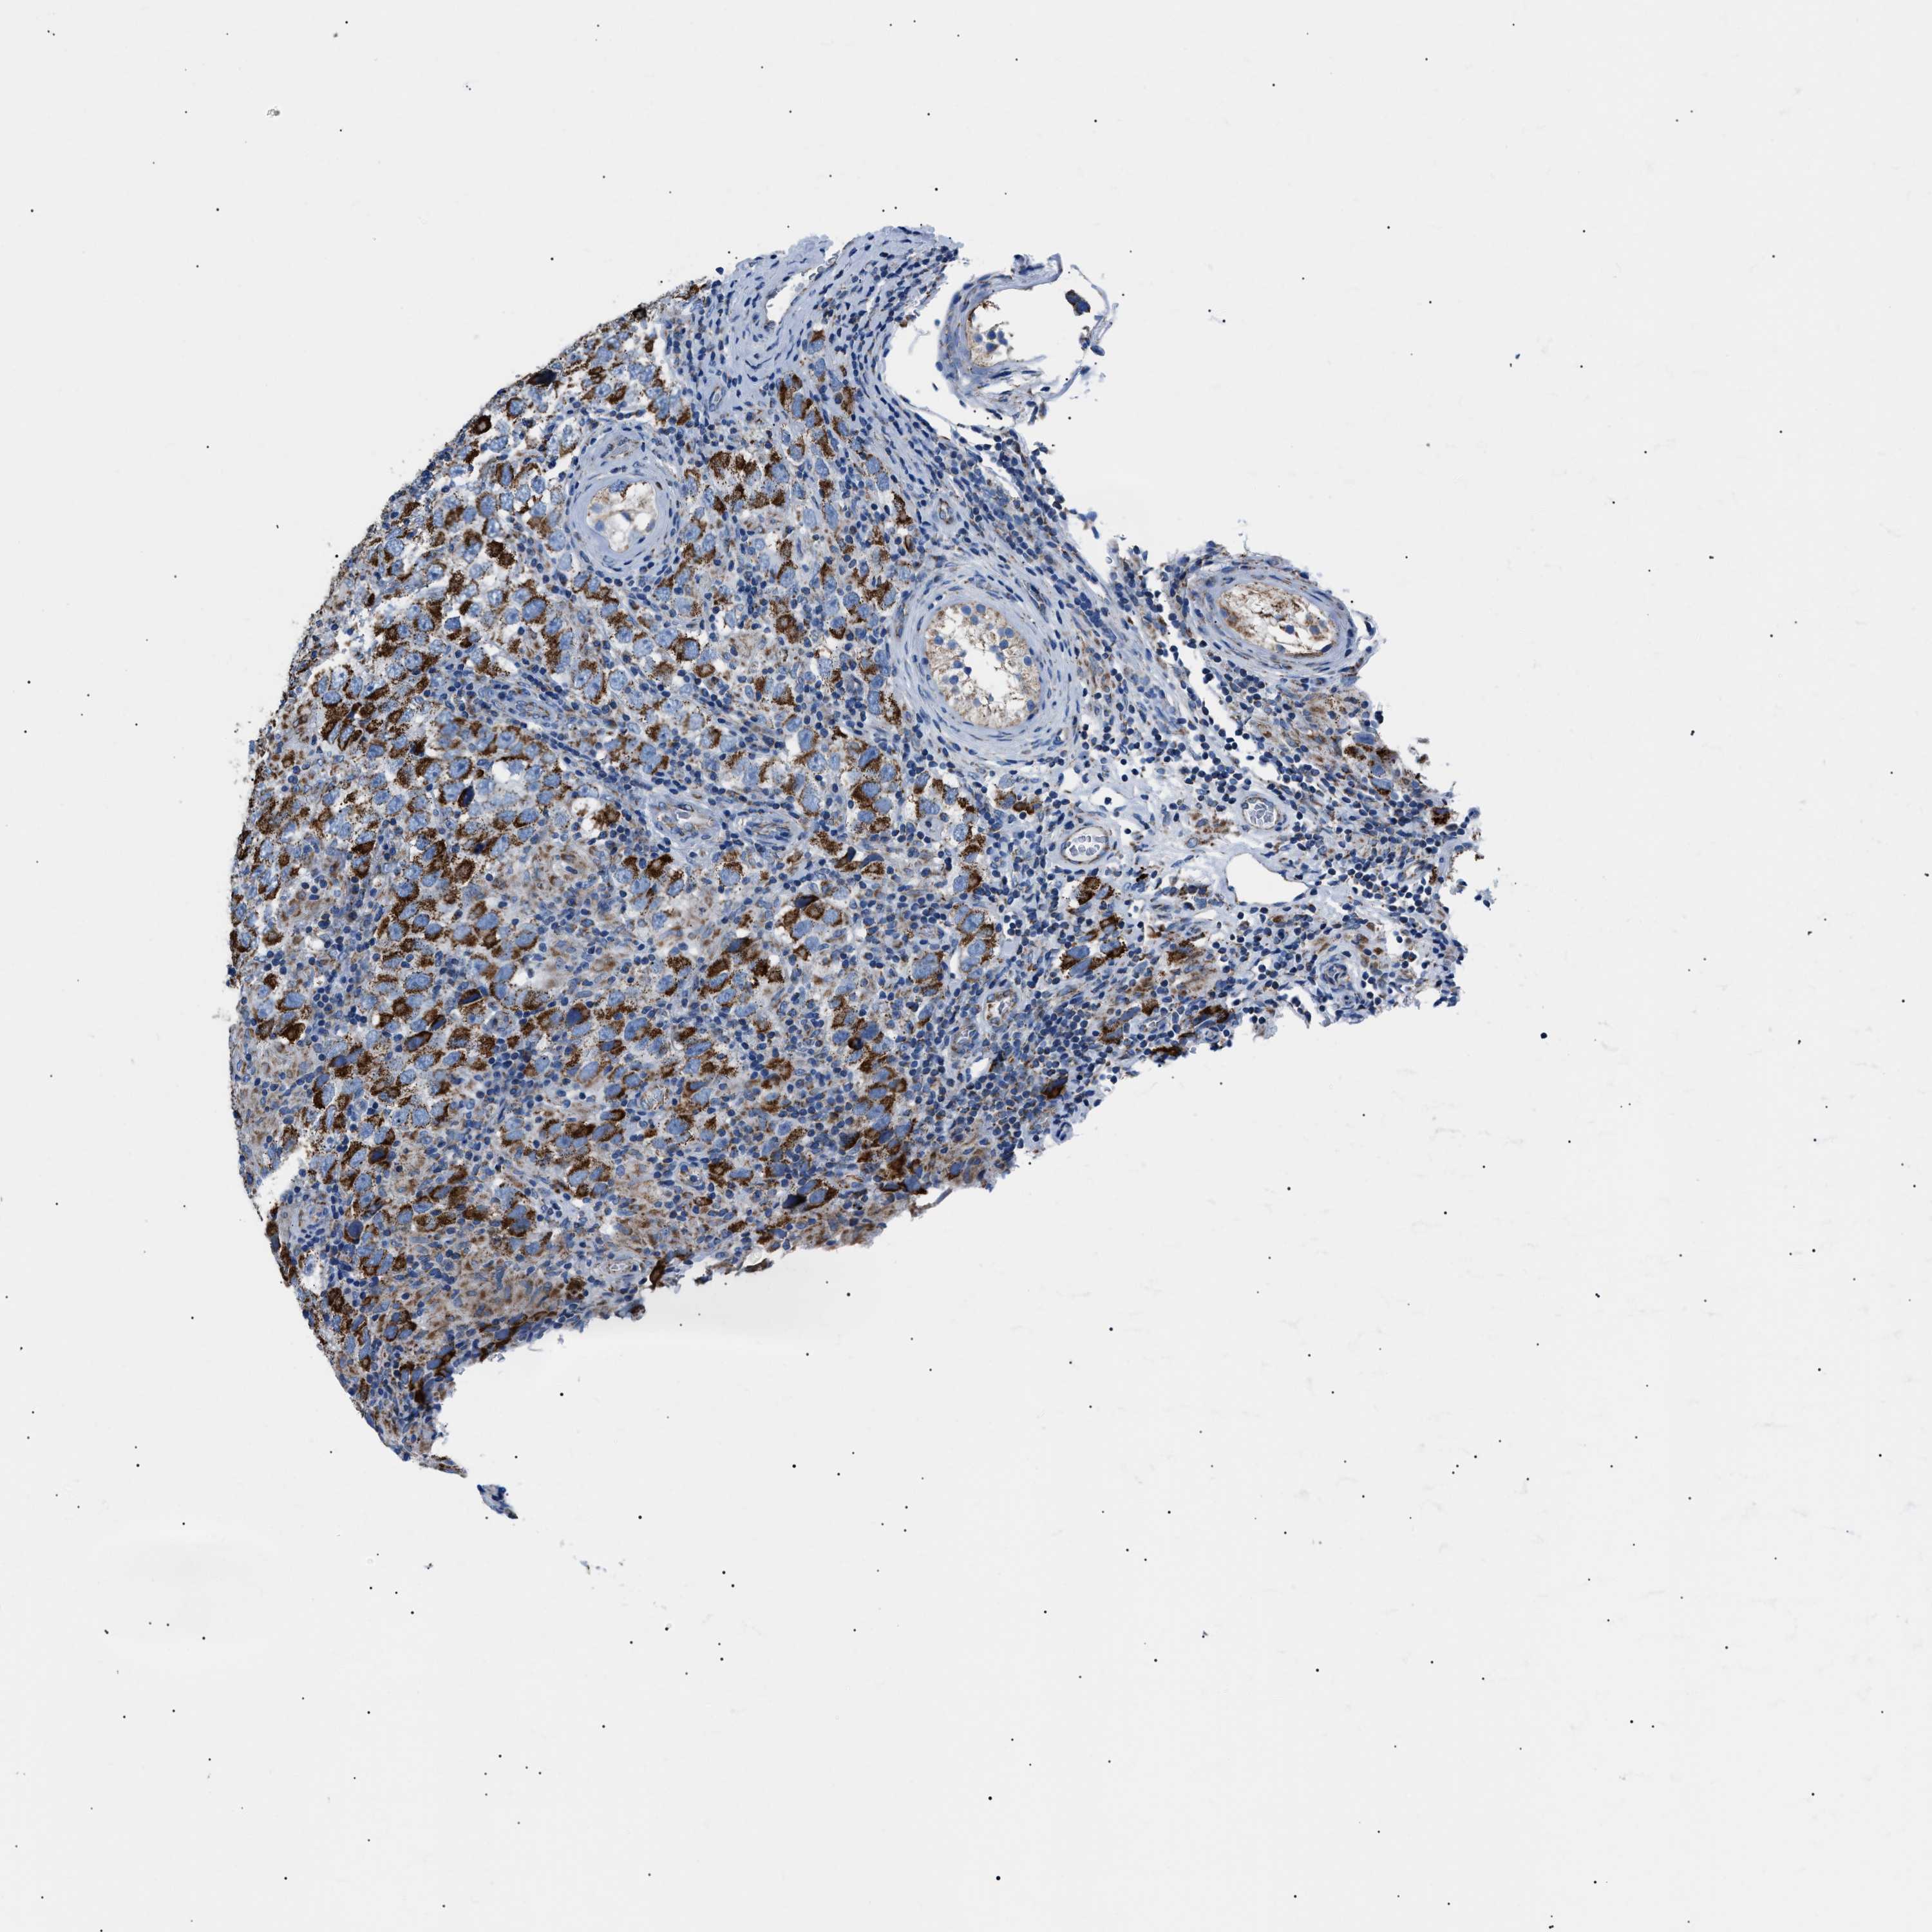

TESTIS CANCER - Protein expressioni

A mouse-over function shows sample information and annotation data. Click on an image to view it in a full screen mode. Samples can be filtered based on level of antibody staining by selecting one or several of the following categories: high, medium, low and not detected. The assay and annotation is described here.

Note that samples used for immunohistochemistry by the Human Protein Atlas do not correspond to samples in the TCGA dataset.

Antibody stainingi

Antibody staining in the annotated cell types in the current human tissue is reported as not detected, low, medium, or high, based on conventional immunohistochemistry profiling in selected tissues. This score is based on the combination of the staining intensity and fraction of stained cells.

Each image is clickable and will lead to virtual microscopy that enables deeper exploration of all samples and also displays staining intensity scores, fraction scores and subcellular localization as well as patient and tissue information for each sample.

Antibody HPA039874

Antibody CAB014889

Antibody CAB026335

Carcinoma, Embryonal, NOS

Seminoma, NOS